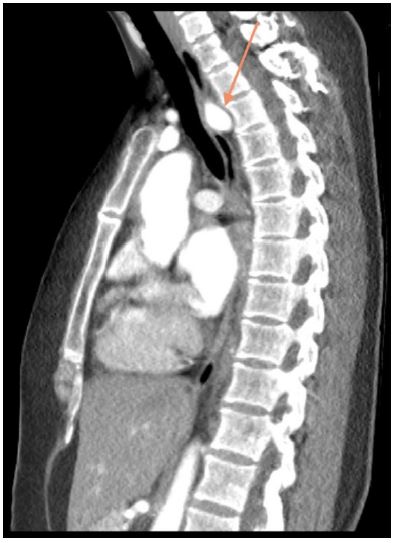

A 39-year-old female with a past medical history of chronic bronchitis presented for evaluation of progressive dysphagia. She reported a long-standing history of difficulty swallowing, often experiencing transient substernal obstruction of solid food and occasionally liquids. Her symptoms subsequently progressed until she was tolerating only minimal oral intake accompanied by unintentional weight loss, prompting her to seek care. A barium esophagram revealed a 2.7 cm extrinsic compression in the upper esophagus. A CT angiogram of the chest identified an aberrant right subclavian artery compressing the esophagus. An Esophagogastroduodenoscopy (EGD) confirmed extrinsic compression in the upper third of the esophagus, consistent with suspected dysphagia lusoria. Esophageal biopsy showed normal mucosa. She underwent right subclavian to carotid transposition and Thoracic Aneurysm Endovascular Repair (TAVER). At a follow-up assessment two weeks postoperatively, she reported complete resolution of dysphagia.

Dysphagia lusoria is a rare condition that occurs secondary to extrinsic esophageal compression by an aberrant right subclavian artery [1]. An aberrant right subclavian artery has a prevalence of 0.16-4.4% [2]. This anomaly is symptomatic in about 30% of cases identified by Figure 2. Dysphagia is the most common related symptom, reported in 90% of cases [1,2]. Other reported symptoms include cough, dyspnea, and chest pain [3].

Figure 2: CT Angiogram (sagittal view) showing an aberrant right subclavian artery with left aortic arch.